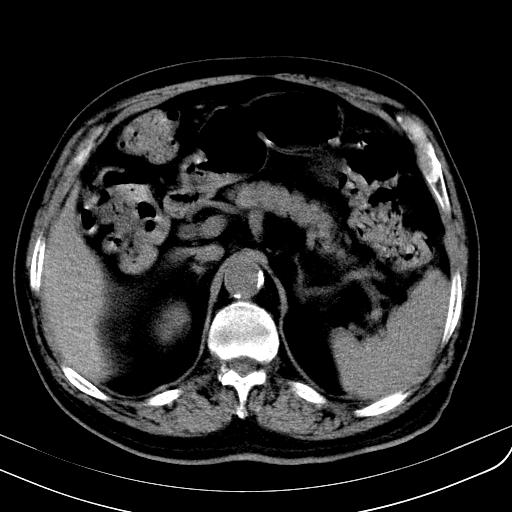

胃底靠近胃大弯处可见一圆形软组织影,直径为3.45cm,ct值约为30.1hu

胃底间质瘤

考虑为胃底间质瘤

胃底良性肿瘤,考虑间质瘤

边缘光滑,密度均匀,良性占位,首先考虑平滑肌瘤。